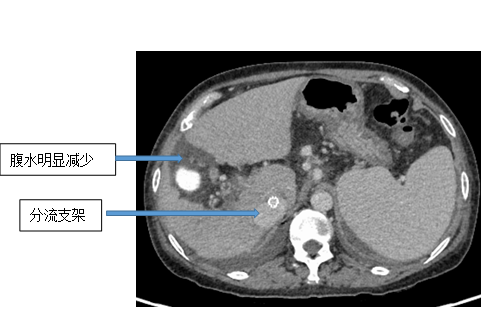

但是湯女士情況特殊,她的門靜脈主支以及多個分支有血栓形成,這極大地增加了治療的風險性和難度。徐龍緊急發起了多學科會診。在與患者家屬詳細溝通了手術可能的風險以及做好完善的術前準備後,徐龍帶領團隊為湯女士開展手術治療。在此次治療中,由於湯女士有嚴重的血栓形成,傳統的TIPS治療已經無法實現,在手術室內,徐龍反覆造影、查看患者的腹部血管走行,最終選擇在下腔靜脈與腸系膜上靜脈之間放置了支架,極大地降低了門靜脈壓力,湯女士轉危為安。

對於未出血的肝硬化患者,徐龍建議平時注意飲食,以軟食為主,也可以服用一些非選擇性β受體阻滯劑,比如普萘洛爾等;對於已經發生過食管胃底靜脈曲張破裂出血的病人,內鏡套扎治療或組織膠注射等治療可以有效地預防再次出血;而TIPS治療是當所有治療都無效時挽救生命的好辦法。它的原理是在X線透視導引下,建立肝內的位於肝靜脈及門靜脈主要分支之間的人工分流通道,從而降低門脈高壓、控制和預防食道胃底靜脈曲張破裂出血,減少甚至消除腹水。